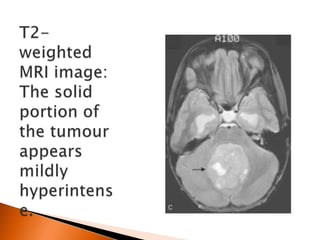

 Medulloblastoma is WHO IV tumor of small

blue cell origin which arise from medullblast

?! cells mostly arise from vermis .

 WHO classification

 Classic 70%

 Desmoplastic /nodular MB 7%

 MB with extensive nodularity (MBEN) 3%

 Large cell /anaplastic variant 10-20%